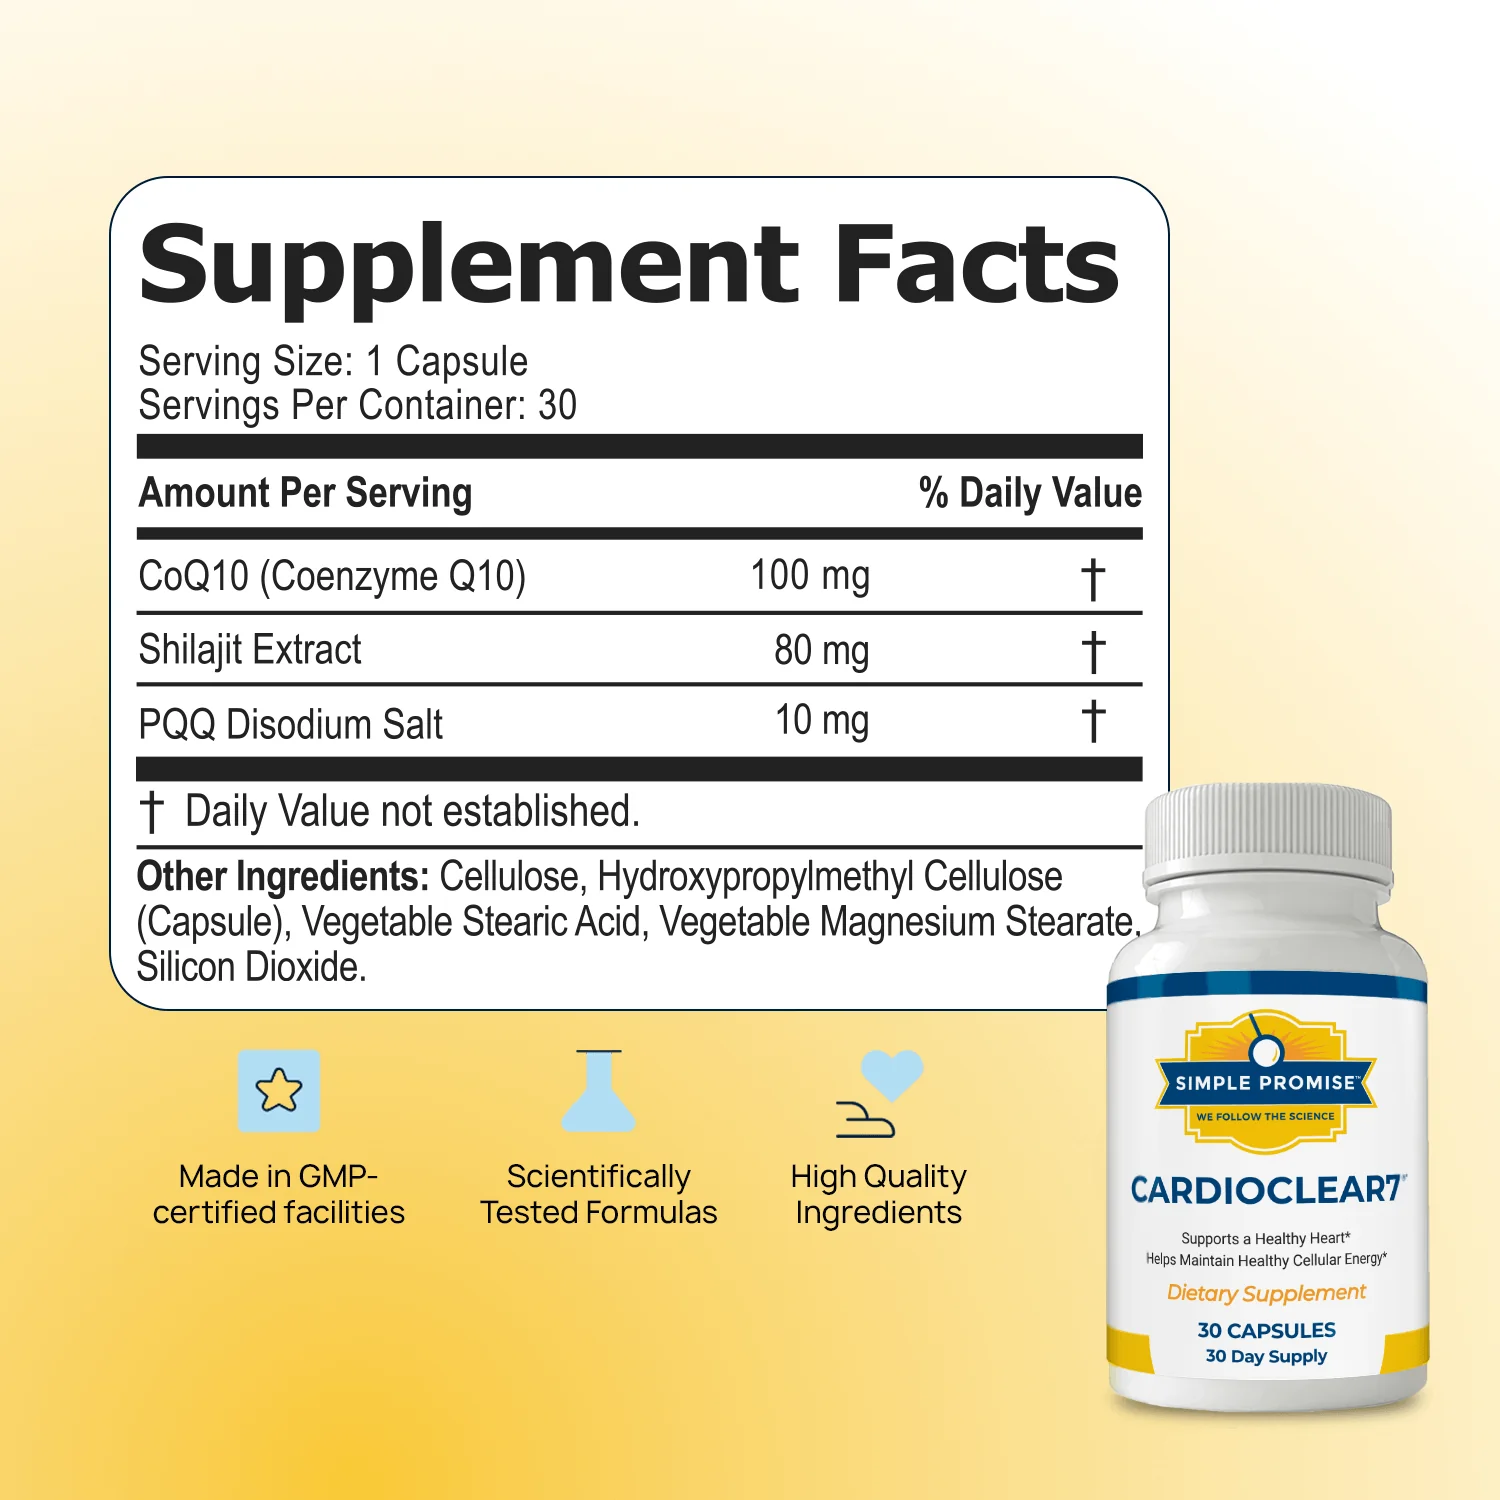

| Ingredients | CoQ10, Shilajit, and PQQ. |

Cardio Clear 7 contains three powerful, science-backed ingredients that work together to support heart health, cellular energy, and mental clarity:

CoQ10 (Coenzyme Q10)

CoQ10 is included to fuel mitochondria, the energy-producing powerhouses of your cells. It helps convert food into cellular energy, protects LDL cholesterol from oxidation, and supports healthy arteries and cardiovascular function.

Shilajit Extract

Shilajit is added to amplify CoQ10’s effects, boost mental clarity, and maintain alertness and focus. It also supports heart health and increases overall energy levels, helping the body perform at its best.

PQQ Disodium Salt

PQQ is included to stimulate the growth of new mitochondria, enhancing the body’s capacity to produce cellular energy. It works synergistically with CoQ10 and Shilajit to revitalize energy production, support brain function, and strengthen cardiovascular performance.

As a dietary supplement, adults are advised to take one (1) capsule daily, ideally 20–30 minutes before a meal. It should be taken with an 8 oz. glass of water to ensure proper absorption.